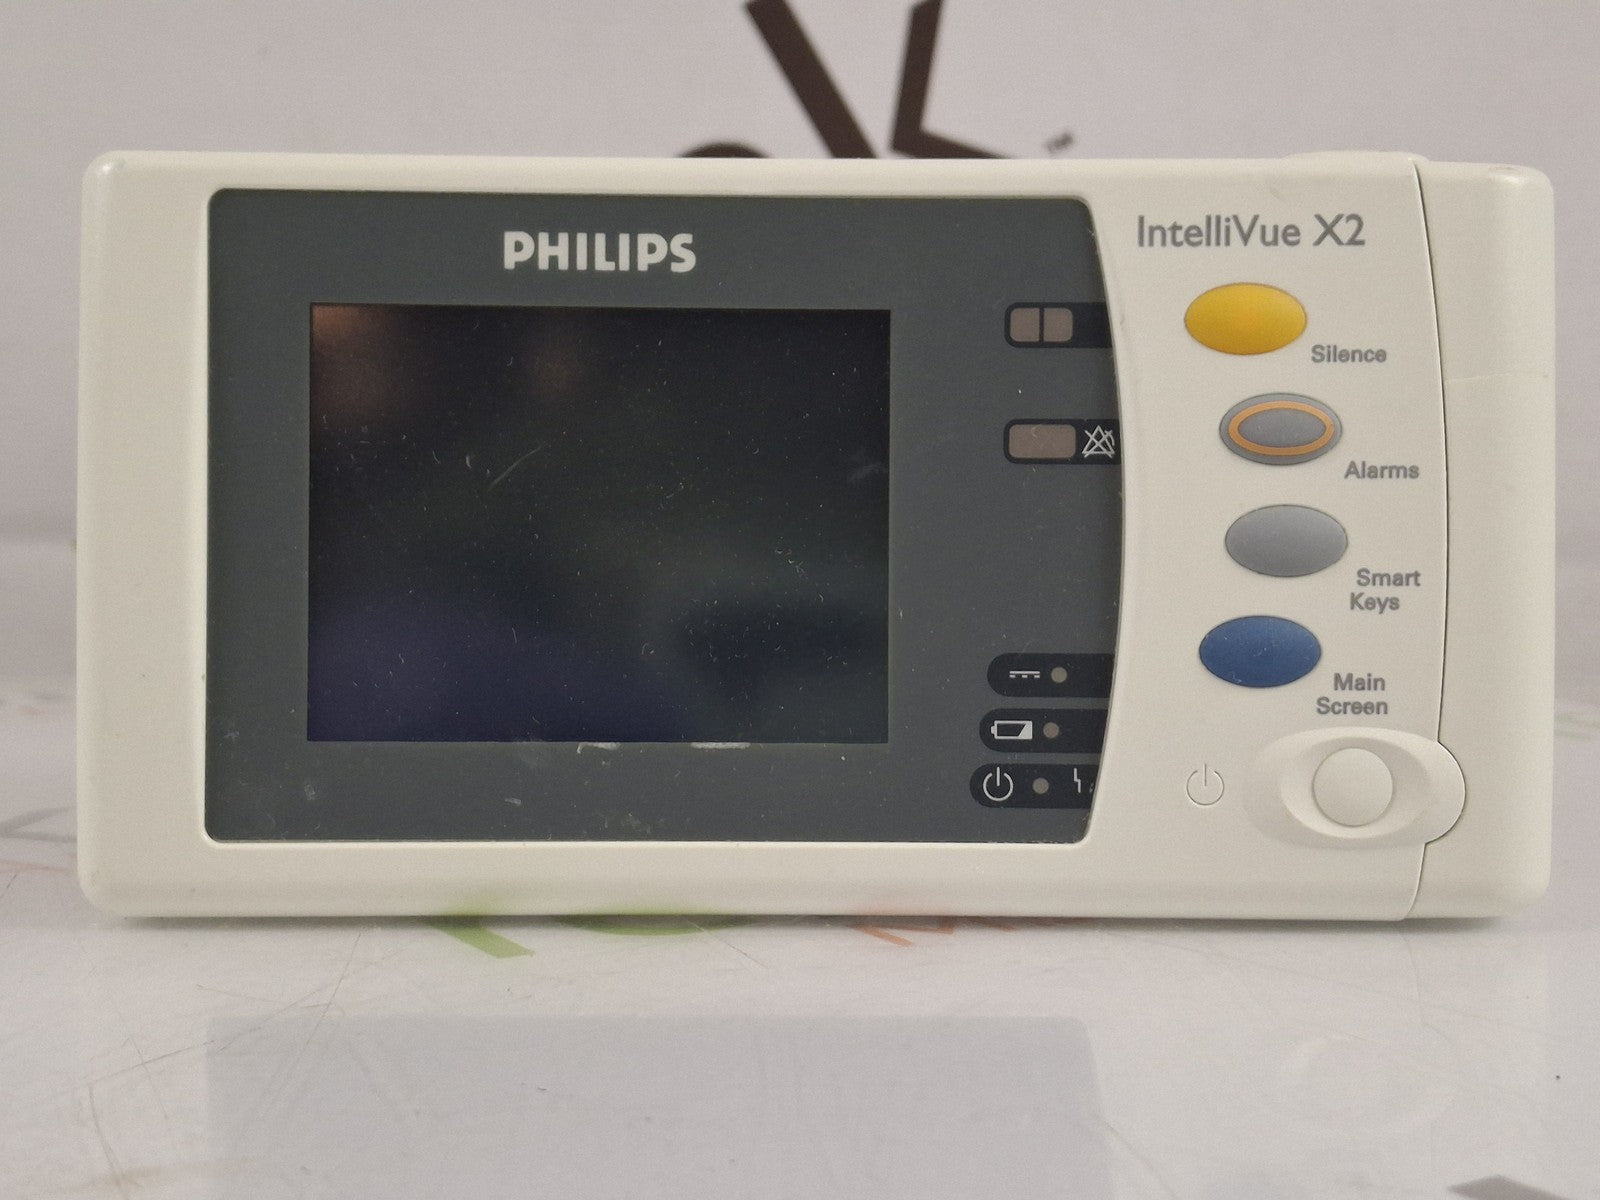

PHILIPS INTELLIVUE MX450 BEDSIDE PATIENT MONITOR

Sale price$ 1,500.00

PHILIPS INTELLIVUE MX450 BEDSIDE PATIENT MONITOR

Sale price$ 1,500.00